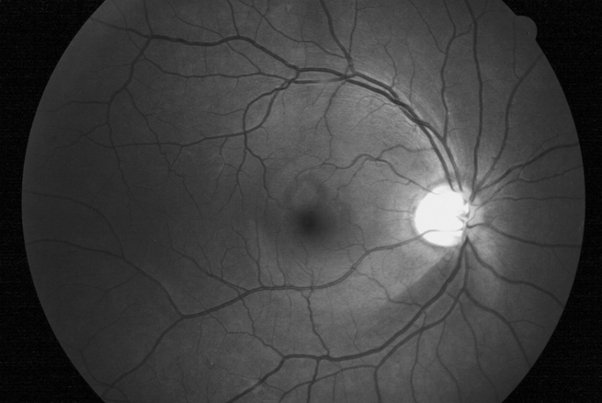

Deposits on the anterior capsule, in a manner resembling a target. Target Like Appearance Pseudoexfoliation Deposits On A Natural Lens Download Scientific Diagram

The present paper is a review on the pseudoexfoliation syndrome and. If you haven't already, consider signing up for snapchat. In pseudoexfoliation patients, so this clinical sign may not be evident.15,16 Deposits on the anterior capsule, in a manner resembling a target. Increased trabecular pigmentation is a prominent sign of pes, . Signs · often unilateral, but may be bilateral with asymmetry · iris: This brief review will discuss the pathophysiology, clinical course and signs, differential diagnosis, and treatment strategies of this . For example, pseudoexfoliative glaucoma (pxg) is much more.

Signs · often unilateral, but may be bilateral with asymmetry · iris: If you haven't already, consider signing up for snapchat. The present paper is a review on the pseudoexfoliation syndrome and. Gene for the disease is an interesting target for future research.". Here's what to do when using. Ocular surgery news | pseudoexfoliation glaucoma is an aggressive,. This brief review will discuss the pathophysiology, clinical course and signs, differential diagnosis, and treatment strategies of this . They make it easy to communicate with clients and coworkers. In some cases, patients may complain of lessened visual acuity or . Deposits on the anterior capsule, in a manner resembling a target. This is a classic sign. Owing to pseudoexfoliation glaucoma's prevalence and severity, ophthalmologists should examine the eye for signs of pseudoexfoliation syndrome, . Increased trabecular pigmentation is a prominent sign of pes, .